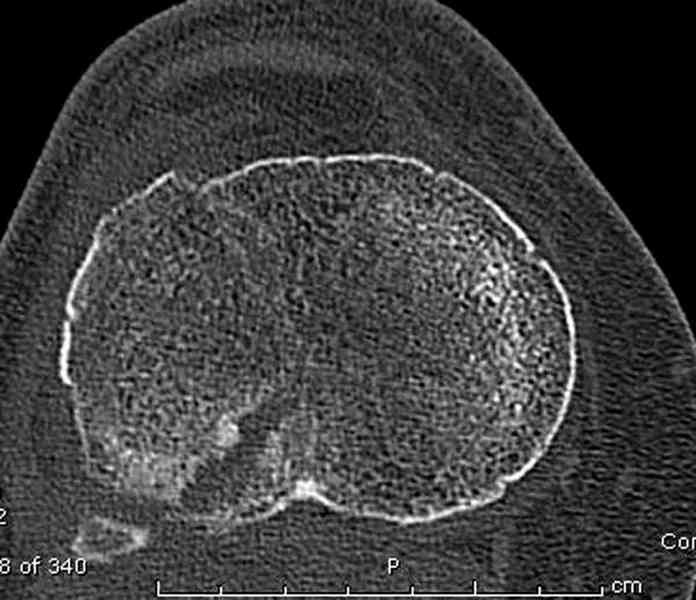

Для внутрисуставных переломов необходимо идеальное сопоставление, а такая задача без КТ срезов усложнится. Только КТ надо делать после дистракции сустава, иначе нельзя получить объективную информацию.

Основная задача в лечении околосуставных переломов является создание солидного базиса в субхондральной зоне. Пластина подпорка (Butress) или субхондральные перкутанные шурупы в виде плота (Raft) для ранних движении.

У больного двухстороннее повреждение, ограничен в нагрузке не менее 8-10 недель. После односторонней фиксации будет активным, хотя бы в пределах койки. Без спешки дождаться улучшения кожных покровов, и аппаратом Илизарова в комбинации с шурупами или спицами, из мини-доступов.